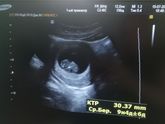

Девочки всем привет!!! Мне врач сказала 15 идти на скрининг, а 19 она меня на учёт поставит, я вот думаю не рано ли она меня отправила? Получается там будет 10 недель и два дня всего?.